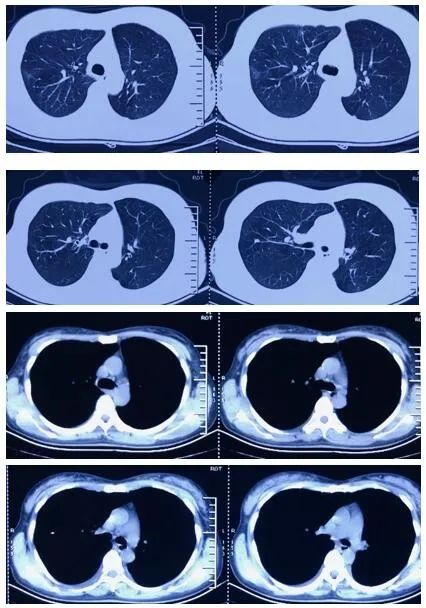

于1月21日受凉后开始出现咳嗽,无痰,无明显发热,至河北省中医院门诊查血常规:WBC 9.84×109/L N7.0×109/L L1.56×109/L,予以口服阿奇霉素0.25g/d 6天,咳嗽症状未见明显变化。2月6日咳嗽症状加重,咳黄痰,至社区卫生站就诊,查血常规:WBC 12.36×109/L N9.41×109/L L2.11×109/L,查胸片示:支气管炎、左肺结节、左下肺结节及条索,静点头孢呋辛、炎琥宁后2天,患者出现发热,体温最高37.6℃,咳嗽加重。2月9日再次因发热就诊于河北省中医院,发热门诊查血常规:WBC 6.1×109/L N 3.82×109/L L1.84×109/L,胸部CT示:双肺上叶少量炎症,双肺少量陈旧性病变,左下肺胸膜处占位。收入隔离病房观察,采咽试子查2次新冠病毒核酸阴性后,2月12日以“肺炎、左下肺占位”收入呼吸科病房单间继续治疗。

初始诊疗思路:肺炎按照2016成年人CAP指南治疗,左下肺占位,片状密度增高,边界清晰,内部密度不均,伴钙化,无支气管影,需要鉴别肺炎、肺隔离症、肺肿瘤、肺不张等,胸部增强CT有助于通过特征征象鉴别上述疾病。

2月19日复查胸部增强CT:上叶病变同前,左肺下叶新磨玻璃影,炎症?左侧肺隔离症(左心房供血罕见)。

本例患者属叶外型,由左心房供血,较为罕见。